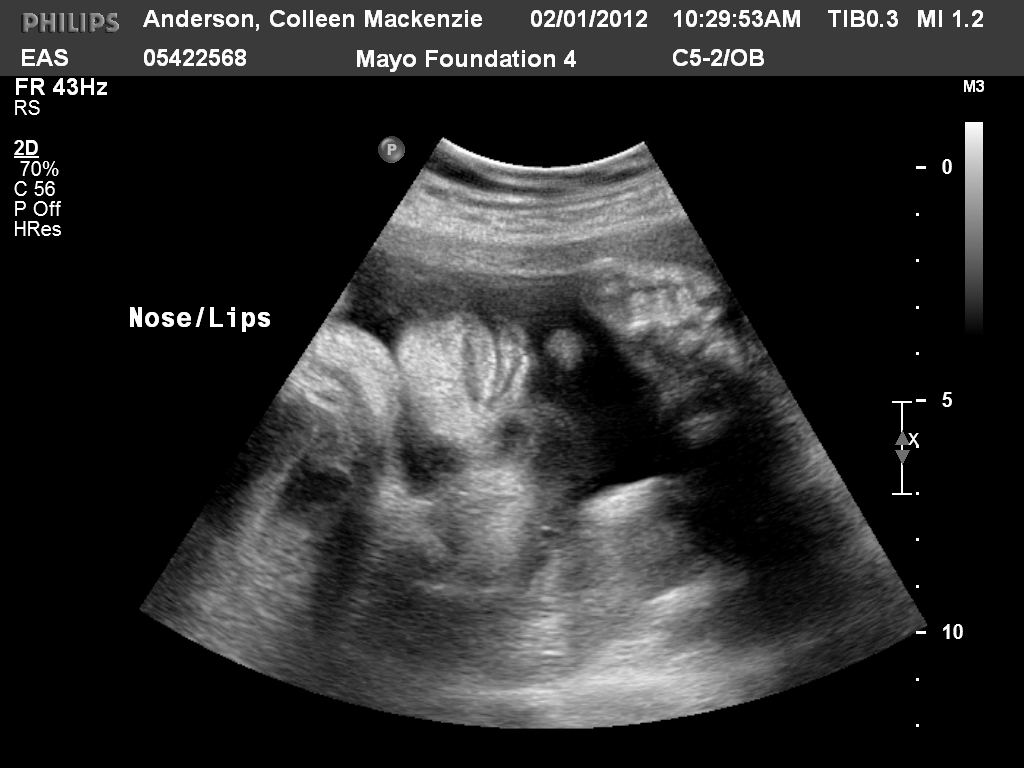

And if you weren't already sick enough of my ultrasound pictures, I have a few more to share!

| Here you can see the tip of her nose and her lips.  I think they look quite feminine in this one!  Pouty, in fact... |